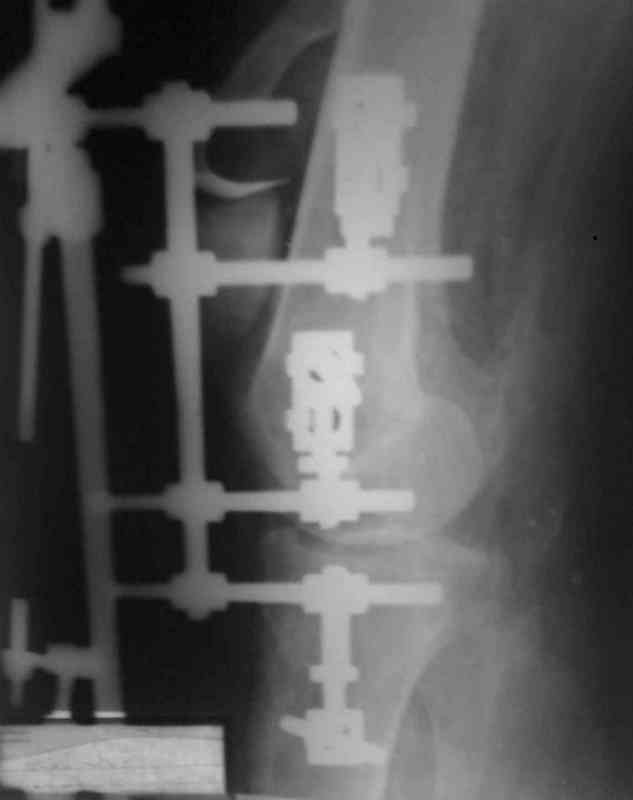

Uvajaemiy kollega! *Pomosh okazano v nujnom ob`eme*- kak ponyat? Vosstanovili krestoobraznih i bokovih svyazok? ili prosto vivih vpravili i fiksirovali AVF. sudya po R-snimkam nadkolennik nahoditsya visoko- znachit povrejdena i sobstvennaya svyazka, kotoraya ne ushita. Potom mojno sostavit plan lecheniya. S uvajeniem Abdurashid.

На ренгенограмме хорошая аппозиция костей коленного сустава, но надколенник находится подозрительно высоко, поэтому необходимо убедиться в отсутствии повреждения связки надколенника.

Аппарат внешней фиксации удаляется в 6-7 недель,

предпочтительно под общим обезболиванием, во время

удаления проверяется стабильность и амплитуда движения в коленном суставе с редрессацией.

При пользовании стержневых наружных фиксаторов,

надо придерживаться правила проведения стержней подальше от зоны, на бедре лучше накладывать стержни косо передне-латерально, между брюшками прямой и vastus lateralis, а на голени по передне-медиальной поверхности большеберцовой кости, где отсутствует мышцы, иначе

восстановление движения в суставе тяжелее из-за

прошитых мышц спицами или стержнями аппарата.